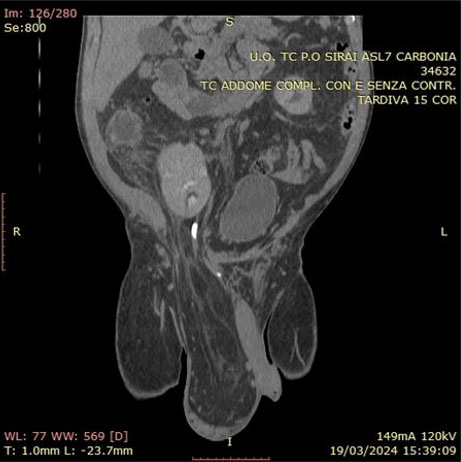

An 89-year-old man was admitted to the Department of Urology for testicular swelling and tenderness for five months with associated comorbidities of urolithiasis, atrial fibrillation in oral anticoagulant therapy, pleuritis, and hypertension. His testicular tumor markers [alpha-fetoprotein (AFP), beta-human chorionic gonadotropin (β-hCG), and lactate dehydrogenase (LDH)] were normal. A physical examination revealed a right testicular mass with normal skin and left testicle without abnormalities. Scrotal ultrasound (Figure 1) showed the presence of a large (4.16 × 2.26 cm) tumor with circular dichroism (CD) signal occupying the whole right testicle with heterogeneous echogenicity and smaller anechoic cystic components with minimal presence of normal testicular tissue. The left testicle was normal. A total-body computed tomography (CT) scan was performed and showed no signs of metastatic disease or lymphadenopathy. On suspicion of testicular cancer a right-sided radical orchiectomy was performed. Surgery was uncomplicated and he was discharged the day after the surgery. The patient had a close 12 month follow-up without need of any therapy and was in good condition 22 months after surgery.

Figure 1: Ultrasonic appearance of a right-sided tumor with far heterogeneously echogenic and cystic areas.